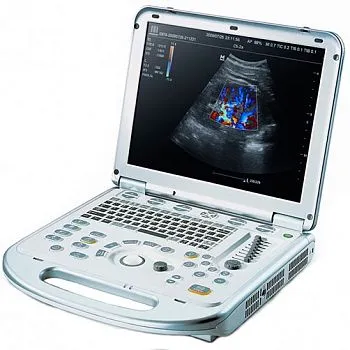

Портативный ультразвуковой аппарат GE Healthcare Logiq e

УЗИ аппарат LOGIQ e — это высочайшее качество визуализации, настоящая универсальность и компактность. Обновленная версия системы — LOGIQ e R9 — обеспечивает ещё более высокий уровень качества изображений для более широкого спектра комплексных исследований, включая интраоперационные и малоинвазивные вмешательства. Аппарат составит достойную конкуренцию стационарным системам среднего и высокого класса, как в плане возможностей, так и цены.

Систему отличает наличие датчиков со сверхвысокими частотами сканирования, эталонная чувствительность доплеровских режимов для сосудистых исследований, в том числе наиболее сложных транскраниальных, а также высокая частота кадров, которая необходима для качественных кардиологических исследований.

Портативный ультразвуковой сканер Logiq e одинаково эффективно решает диагностические задачи при проведении абдоминальных, сосудистых, кардиологических, акушерско-гинекологических исследований и исследовании поверхностных органов. Позволяет легко работать с разными пациентами от новорожденных до взрослых с «лишним весом».